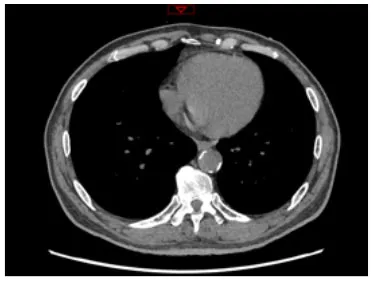

Moreover, the clinical-epidemiological features and lack of non-invasive specific diagnostic indicators, especially for microcalcification, are not well understood. VC especially coronary artery calcification (CAC) significantly increases the difficulty of percutaneous coronary intervention (PCI), and preevaluation of CAC lesions has a critical impact on subsequent treatment. Many imaging technologies have evolved in recent years to aid in the evaluation of calcified lesions, therefore, reducing the danger of intervention and improving the prognosis of surgery. These testing approaches have their own set of pros and cons, which are briefly summarized in Table 1. The diagnosis of microcalcifications mainly relies on optical coherence tomography (OCT) and 18FU-CT, both of which are invasive and expensive (172). Therefore, there is an urgent need to find methods and molecular markers for the non-invasive identification of early microcalcifications and to lay the foundation for the development of effective drugs for the treatment of or stabilization of microcalcifications.

Table 1

| Imaging modalities | CT | Coronary angiography | IVUS | OCT |

|---|---|---|---|---|

| Representative images | ![]() | ![]() | ![]() | ![]() |

| Invasive | No | Yes | Yes | Yes |

| Max resolution | 0.4–0.6 mm | NA | 100–200 μm | 10–20 μm |

| Notable shortcomings | Inadequate spatial resolution for detecting microcalcifications | Low resolution | It cannot determine the depth of calcification. | Expensive and prevents visualization of deep calcium |

| Sensitivity | *** | * | *** | **** |

| Location determination | *** | * | *** | **** |

| Quantitative analysis | *** | * | ** | **** |

Comparison of different methods for the examination of calcified lesions.

*~**** symbol indicates detection sensitivity/ability.